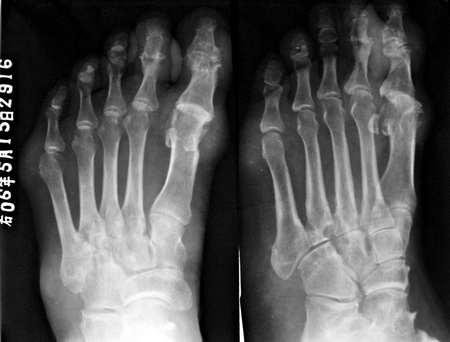

不用病史大家一看就知道是什么了!

痛风。

痛风 典型

痛风.并且可见到痛风石

支持痛风---穿凿状破坏,软组织肿块,痛风石形成。

穿凿样骨质破坏及及足、外踝痛风结节形成符合痛风性关节炎。

尿酸高,该患者患病已经近十年,双手及双足均可见多发明显病变。